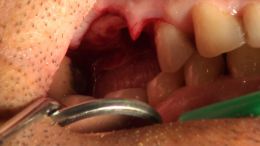

اصول مبانی GBR

+ اساتید گروه علمی بن تاژ پارس (زیرنظر پروفسور غلامی)

- جراحي توسط دکتر عميد از اساتید گروه علمی بن تاژ